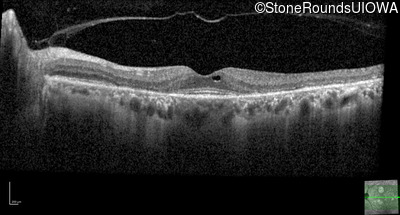

Optical Coherence Tomography - Right - 20/20

Exemplar / OCT Stack

OCT Stack